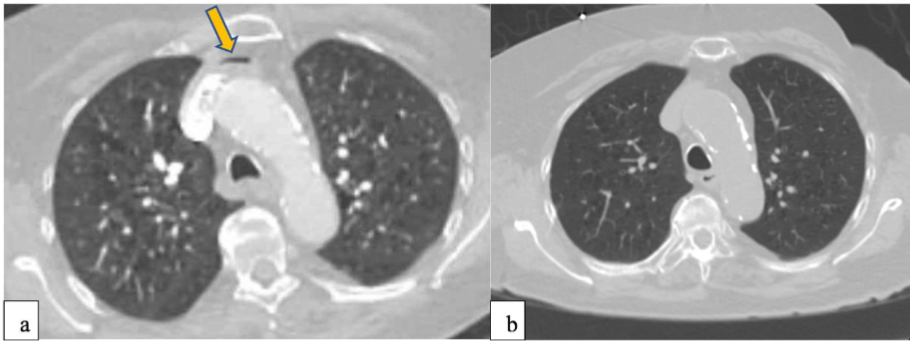

PERCUTANEOUS TRANSTHORACIC LUNG BIOPSY:

Given the highly vascularized nature of the lung, it is no surprise that air embolism can occur after lung trauma. Similarly, air embolisms can occur after Percutaneous Transthoracic Lung Biopsy (PTLB). In a systematic review, the combined incidence of air embolism after PTLB was found to be 0.08% and one third of these patients suffered disease sequelae or died. The same study also noted an increase in air embolism events and more adverse outcomes with aspiration biopsy compared to core biopsy.